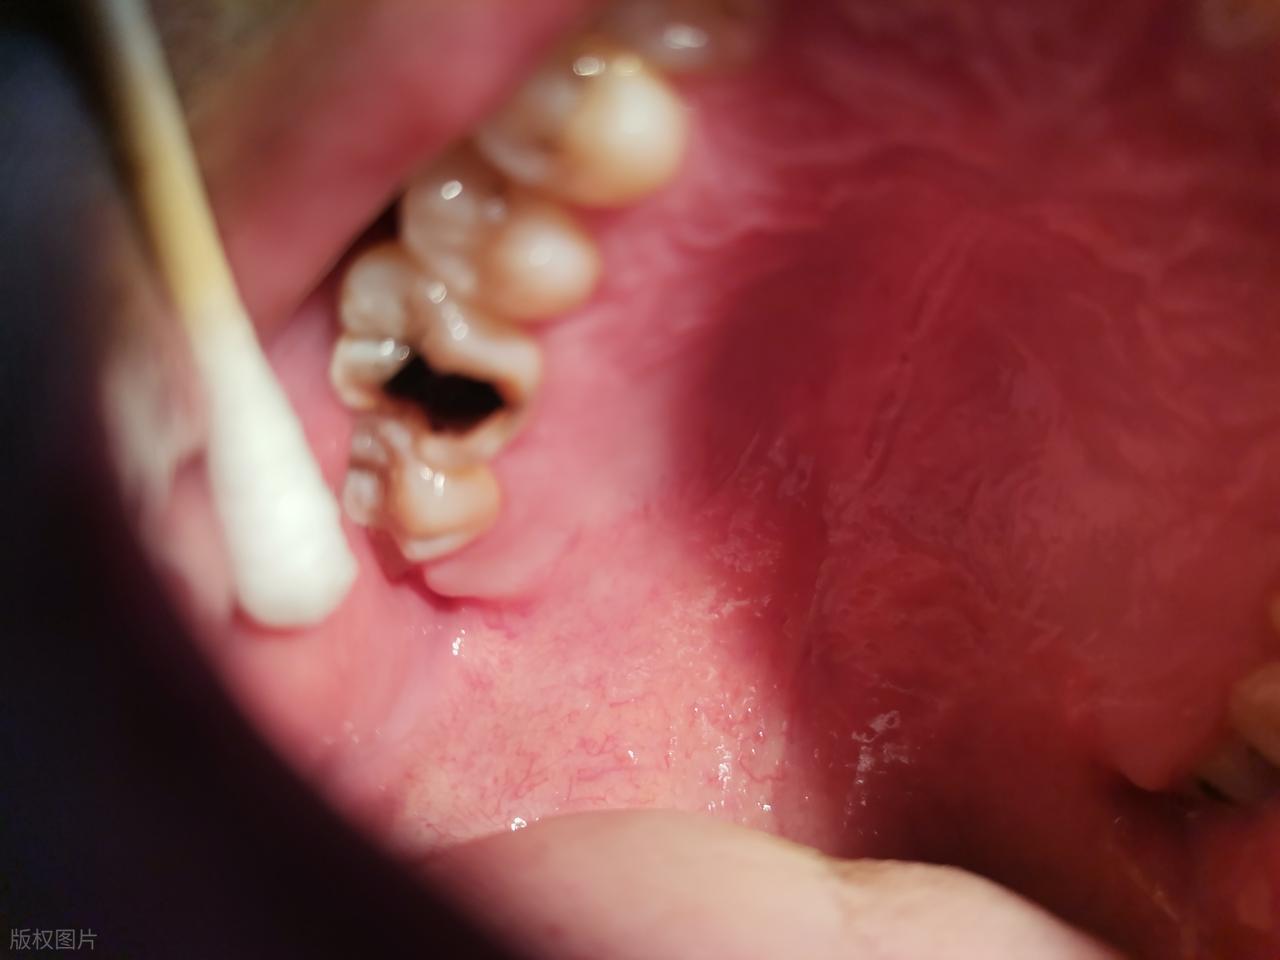

橫着長的智齒無法正常萌出,牙冠周圍會形成盲袋,食物殘渣和細菌易在此堆積。當身體抵抗力下降時,盲袋內細菌大量繁殖,就會引發智齒冠周炎,出現牙齦腫脹、疼痛,嚴重時甚至會導致張口困難、發熱等症狀。這種炎症往往會反覆發作,影響日常生活和進食。